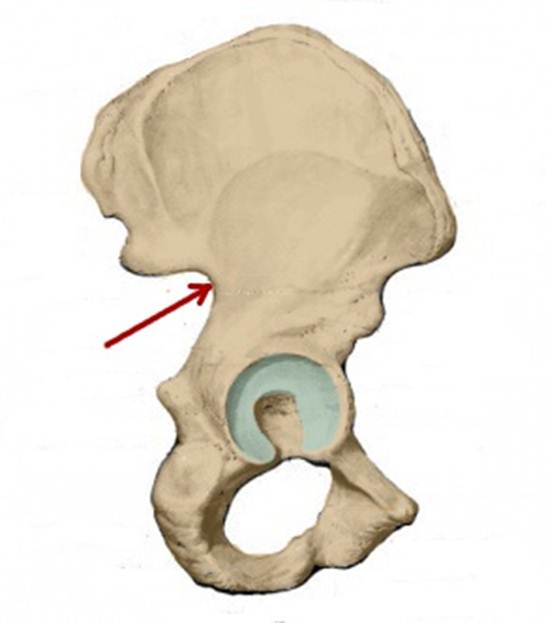

S:Стрелка указывает на spina iliaca posterior superior

S:Стрелка указывает на lambium internum

S: Стрелка указывает на spina iliaca posterior inferior

S: Стрелка указывает на facies auricularis

S: Стрелка указывает на facies sacropelvica

S: Стрелка указывает на eminentia iliopubica